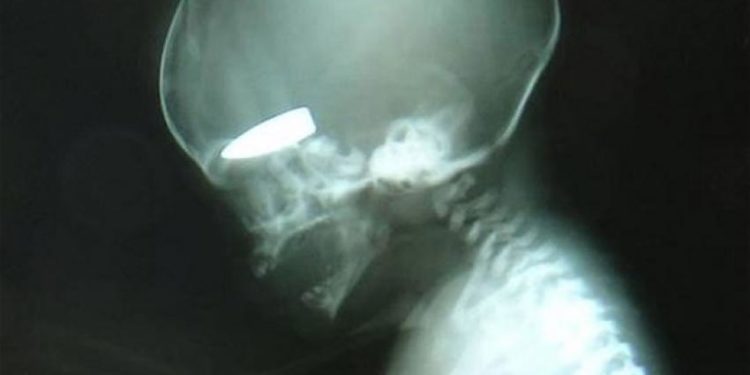

Έγκυες γυναίκες είναι στόχοι ελεύθερων σκοπευτών στη Συρία και μάλιστα “επιβραβεύονται” μ΄ αυτό με μερικά πακέτα τσιγάρα. Η αποκάλυψη που δημοσιεύεται στην βρετανική εφημερίδα Telegraph, είναι ανατριχιαστική και συνοδεύεται από τη φωτογραφία ενός εμβρυου στο οποίο έχει “καρφωθεί” η σφαίρα ενός ελεύθερου σκοπευτή.

Το ρεπορτάζ της εφημερίδας υποστηρίζει ότι αυτές τις βολές τις κάνουν ελέυθερεοι σκοπευτές του Άσαντ οι οποίοι έχουν λάβει σχετικές εντολές να “προτιμούν” ως στόχους τις έγκυες γυναίκες. Και για κάθε τέτοιο στόχο αμείβονται με μερικά πακέτα τσιγάρα!

Σε μία μόνο ημέρα περισσότερες από έξι έγκυες γυναίκες είχαν χτυπηθεί από πυρά ελεύθερων σκοπευτών. Οι περισσότερες επιβίωσαν όχι όμως και τα έμβρυα.

Η βρετανική εφημερίδα δημοσιεύει τη φωτογραφία της ακτινογραφίας που δείχνει ένα έμβρυο να έχει σφηνωμένο στο κρανίο του μια σφαίρα .